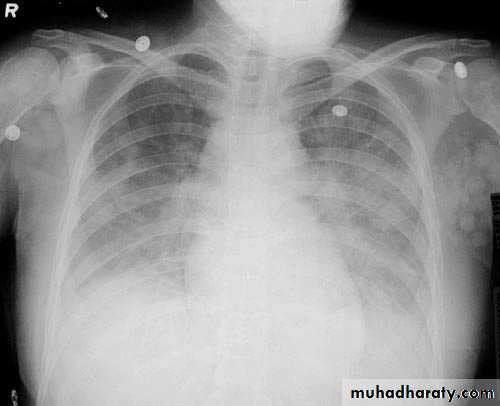

Interstitial pulmonary edema

Pulmonary edema ( alveolar pulmonary edema)

38.interstial pulmonary edema

39.pulmonary edema ( alveolar pulmonary edema )